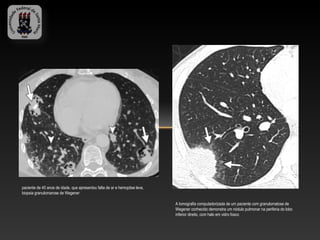

paciente de 40 anos de idade, que apresentou falta de ar e hemoptise leve,

biopsia granulomarose de Wegener

A tomografia computadorizada de um paciente com granulomatose de

Wegener conhecido demonstra um nódulo pulmonar na periferia do lobo

inferior direito, com halo em vidro fosco

paciente de 40anos de idade, que apresentou falta de ar e hemoptise leve, biopsia granulomarose de Wegener A tomografia computadorizada de um paciente com granulomatose de Wegener conhecido demonstra um nódulo pulmonar na periferia do lobo inferior direito, com halo em vidro fosco